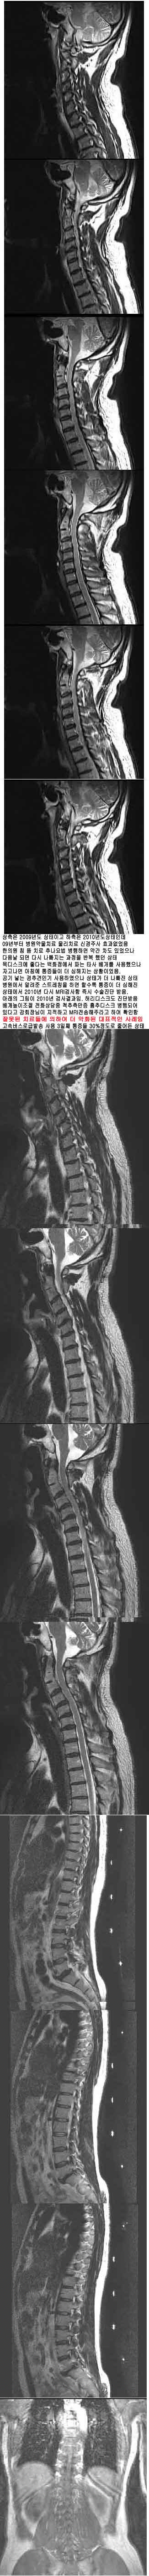

̷ ġ ¿ ȭǰ ־ ؾѴٴ *#ö@& mri ȸ Ǿϴ. ġ ˷ ͳ ü ߸ ƮĪ Ͽ ȭ ǥ 2009 * ̰ 2010 ε 09 ġ ġ Űֻ ȿ . ǿ ħ ġ ߳ ϸ ణ ־ Ǹ ٽ ݺ ߴ ũ ٴ ȭ Ĵ Ÿ ͳݿ ڰ ħ Ȳ̾. ִ ߰α Ͽ ° ͳݰ ġ ǻ簡 ˷ ٴ ƮĪ ϸ Ҽ ¿ Ӽå ٰ 2010 ٽ MRI˻ ũ . Ʒ 2010 ˻. 㸮ũ ܹ ȭ ô ߵũ Ǿ ִٰ ȸԲ ϰ MRIֶ Ͽ Ȯ. ߸ ġ ߸ ü ƮĪ ȭ ǥ ӹ 3° 30% پ ¿ ̱ ۼ. [ֹȣ : 20100921132830y04140] * ֹ ֹϽ : 2010-09-21 13:28:30 +ְ 160ȣ 160-210ȣ γ,ûҳ Ű 168 71 54 ˰Ե ͳ ˻ڷ õ ڸǥغ ϱ ȣϽ 1C.ٺҸ, 1C.ٸǷ 1C.ھ 1C.ټ Ǹ 1C.ٱ () 1C.߷ () 1C.Ƿ () 1C.̸, 1C.ڱ ֺ ̻, 2C.ھȱ, 2C.ڴ, ýŰ , 2C.ڽ÷ 2C.ھȱ, 2C.ڴ 2C.ٴ, 2C. . 2C.ڹ̰̻ 3C.ġ Ű 4C. ֺ 5C.ٸ, 6C.ڸ 6C.ھ Ḳ 6C.ڻ 6C.7C.ھ հ ̳ 7C.Ȳġ 7C. 1T.ڼո 1T.Ȳġ 5T. 6T.ڼȭҷ 7T. 10T.ٸǷ 4L.° 4L. 财, 4L. ϴ 财 5L.ڹ߹ٴ̳ ߵ ̳ ȭŸ̳ 5L.Ƹ 㰡 (). ()ũ( ߰Ż) źϸ Ը ũ(߰Ż), ũ(߰Ż)ġ, հ , , հ , ġ, , Ḳ , , Ḳ ġ ȱ ǰϰų 㸮ũ(߰Ż) ߿ ġ Ƿ ġ 索ġ γ Ȱ ڸǥغ ȣϽ ϰ ߴ ġẴ ǿ ġ ħ ġ αġ ī̷ƽ ߳ ġ غ ϴ ġ ϴٰ ȭDZ 2009 8 ù mri˻系. ߵٰ 3 ȭǰ ؾѴٰ ܹ ᵵ ڰ ϻȰ ---------------------------------------------------------------------------------- 21 ֹϼ̰ 22 ӹ ù 80л 3/10 پ · Ϸڰ 23 Ľð 111 1.5/10 پ· Ͽ Ѻ Ʈ 926 ߰˳Դϴ. Ҹ,- ֹŴϴ. ̸, ֺ ̻,- ʹ Ÿ ʾҴϴ. ȱ, , ýŰ , ȱ, ó ſ ִٰ ϴ. . ̰̻- ϴ. Ư ġῡ ˾ ƹ ִϴ. ġῡ ȣ ڲ ߵǴ Ȳ ̷ ȿ Ÿϴ. ̻, ,- µ ǥغ Ÿ ʾҴϴ. , -- ǥغ ƴ϶ϴ. Ḳ Ȳġ-- پ پ ִ ȲԴϴ. ո , Ȳġ-- ȣ ʴϴ. ȭҷ-- ȭ ǰ ϴϴ. 索, -- 350̴ 2 270 · °, 财, ϴ 财--ٱⰡ 絵 ÿ 㿡 Һ ¶ϴ. ߹ٴ̳ ߵ ̳ ȭŸ̳ , Ƹ 㳪 Ÿ ʾ ø ִϴ. : 21 ֹϼ̰ 22 ӹ ù 80л 3/10 پ · 2010-09-24 14:20:51 Ȩ : Ϸڰ 23 Ľð 111 1.5/10 پ· Ͽ Ѻ 2010-09-24 14:21:07 Ȩ : а ־ Ѵٰ ڸ Ǿ ȸԲ 24 120 ȭϰ پ ٽ 2010-09-25 11:29:06 : ȯںв ε Һ ͵ . ̰ ̻ ˾ ġ ʾҴµ ƹ ִٰ Ͻ. ̺İ 6 ġ ġῡ ڲٸߵǰ . 2010-09-26 12:43:00 : Һٱ , ̻, ó ġῡ ʾҴ 4 ٰ 2010-09-26 12:44:48 : 索 ġ 350̴ 2ϸ ħ 270 . 2010-09-26 12:46:43 11 28 ߰ ˳Դϴ. ƿ е о Ϻʹ ġ ġ ߱ ƮĪ ٽ ϰ ġ ϱ . ġؿ ϰ ̻ û ˽ϴ. |